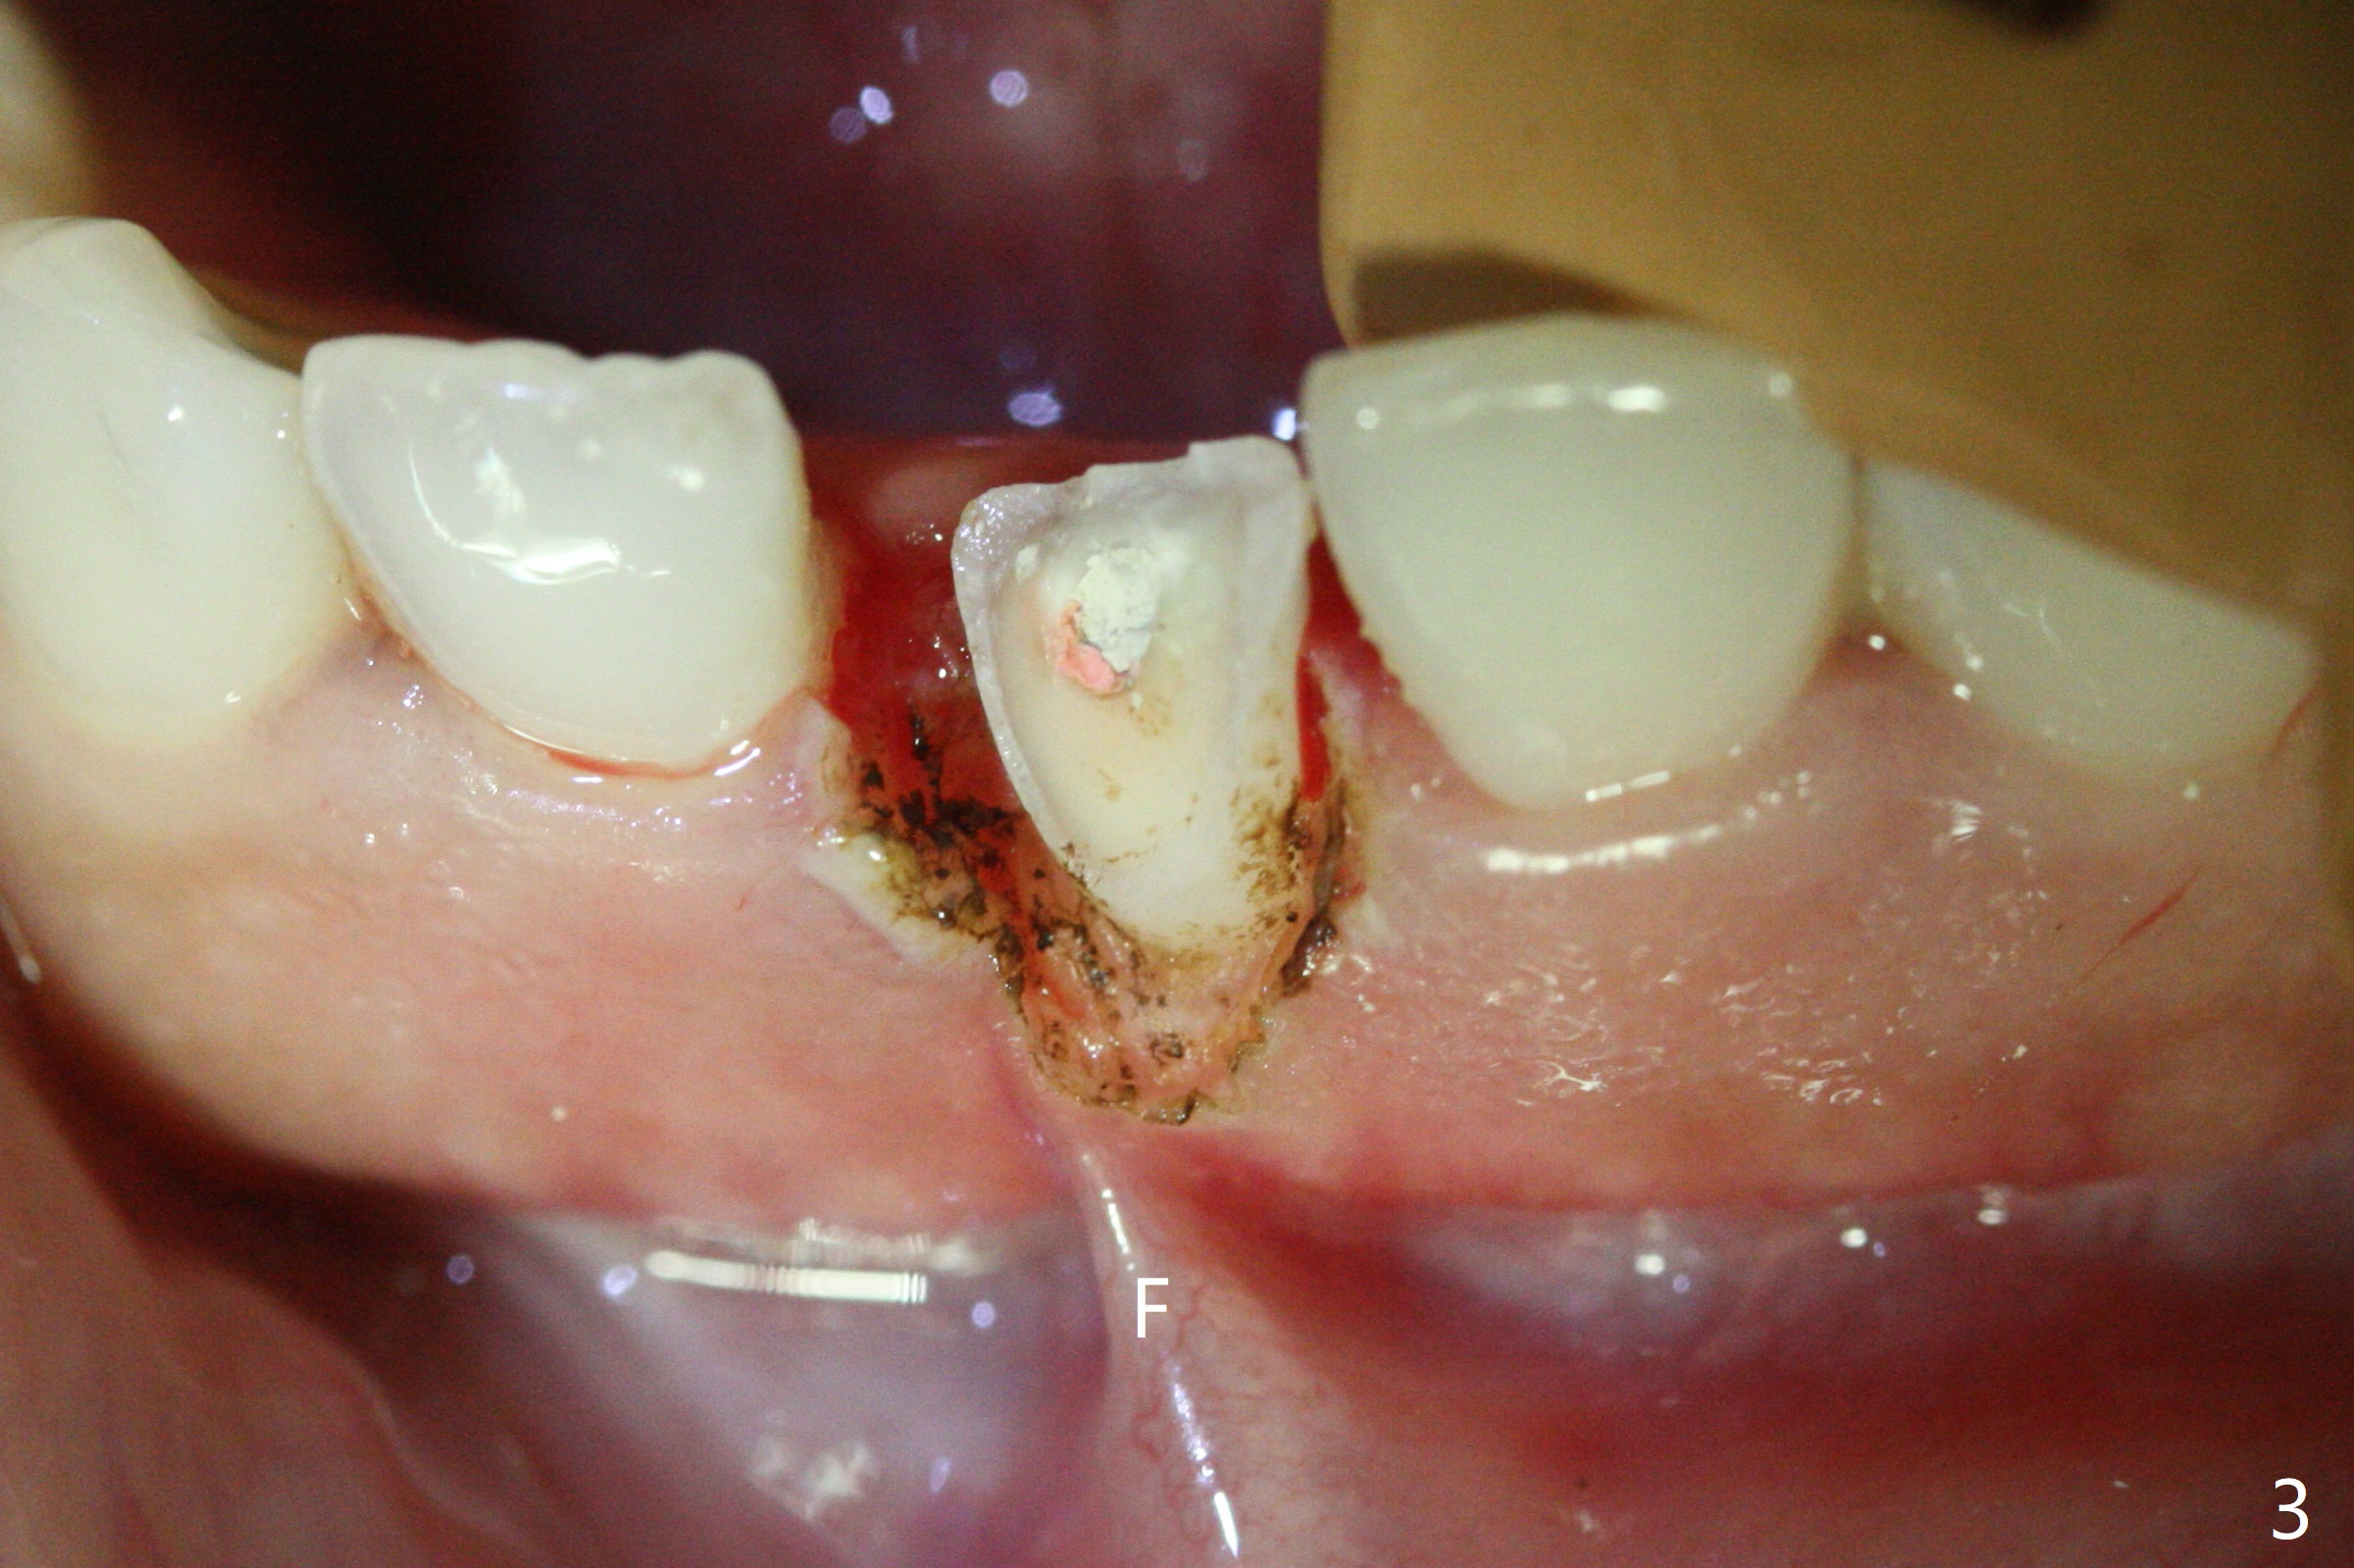

A 31-year-old woman fractured the lower left central incisor when it was hit by her 2-year-old son's head with mesiobuccal subgingival margin (Fig.1). After RCT (Fig.2), gingivectomy is conducted with eletrosurg to expose the fractured margin (Fig.3). In 2 days, a prefabricated fiber post will be bonded with the tooth and the fractured fragment together. To extend the use of the incisor, two implants are required (Fig.4). As scheduled, the patient returns with the fractured portion (Fig.5,6 (buccal (B) and lingual (L) views)). The periodontal dressing is in place (Fig.7 P). After preparation of the post space, the fiber post (Fig.10 (P)) is bonded with resin cement (Fig. 10 ^ and *) to the tooth and fragment with rubber dam (Fig.8). The patient is pleased post occlusal adjustment (Fig.9).